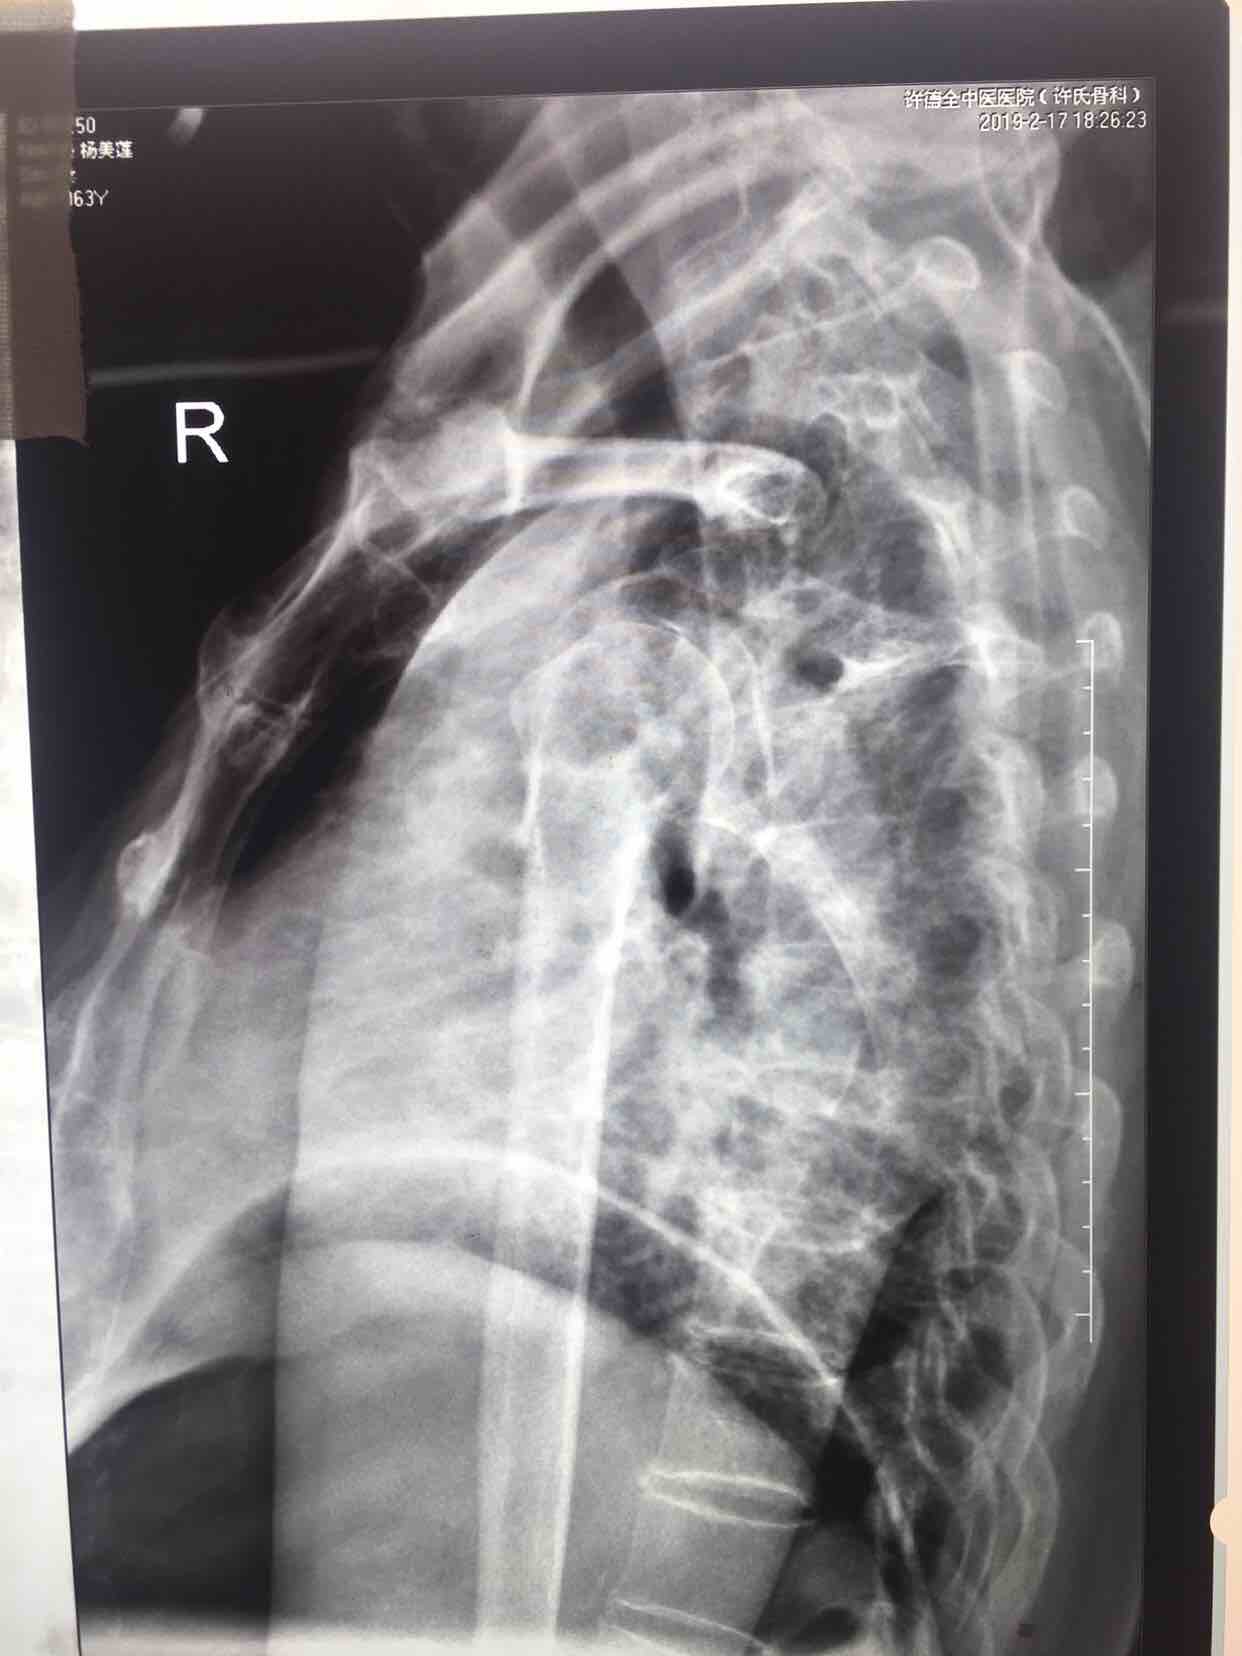

摔伤后右肩部肿痛活动受限1小时入院。既往患高血压5年左右,最高为160/90毫米汞柱。无特殊不良嗜好。

生命体征平稳,心肺腹未见异常。右肩部肿胀明显,局部皮色皮温基本正常,压痛及纵叩痛阳性,可及骨檫音及骨檫感,肩关节活动受限,末梢血运感觉正常。

诊断:肱骨外科颈粉碎性骨折(右)完善术前准备,在臂丛麻醉下行切复内固定术,选肱骨近端锁定钛板,保持稳定性及早期功能锻炼。术后抗炎,消肿等处理。